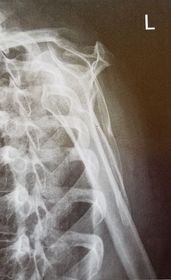

| AP Shoulder internal rotation | the MCP is tilted posteriorly as marked by the superior scapular angle is inferior to the clavicle |

| AP Shoulder | patient is rotated towards the unaffected shoulder: decreased thoracic superimposition over the scapular body |

| AP Shoulder | patient is rotated towards affected side:increased thoracic superimposition over the scapular body |

| Grashey | Insufficient obliquity |

| Grashey | Excessive obliquity |

| Grashey | MCP is tilted posteriorly |

| AP Shoulder Neutral | ANATOMY: proximal humerus, lateral 2/3 of clavicle, open shoulder joint CRITERIA: humeral epicondyles are 45 degrees to the IR neither tubercle should be seen on the humeral head POSITIONING: CR perpendicular @ 1'' inferior to coracoid process |

| AP Shoulder Internal Rotation | CRITERIA: lesser tubercle in profile medially POSITIONING: CR perpendicular @ 1'' inferior to coracoid process |

| AP Shoulder External Rotation | CRITERIA: greater tubercle in profile laterally POSITIONING: CR perpendicular @ 1'' inferior to coracoid process |

| Posterior Oblique Grashey | ANATOMY: glenoid cavity in profile glenohumeral joint center of VOI CRITERIA: open glenoid cavity anterior/posterior rims of glenoid cavity are superimposed POSITIONING: pt in 35-40 degree posterior oblique CR perpendicular @ glenoid cavity |